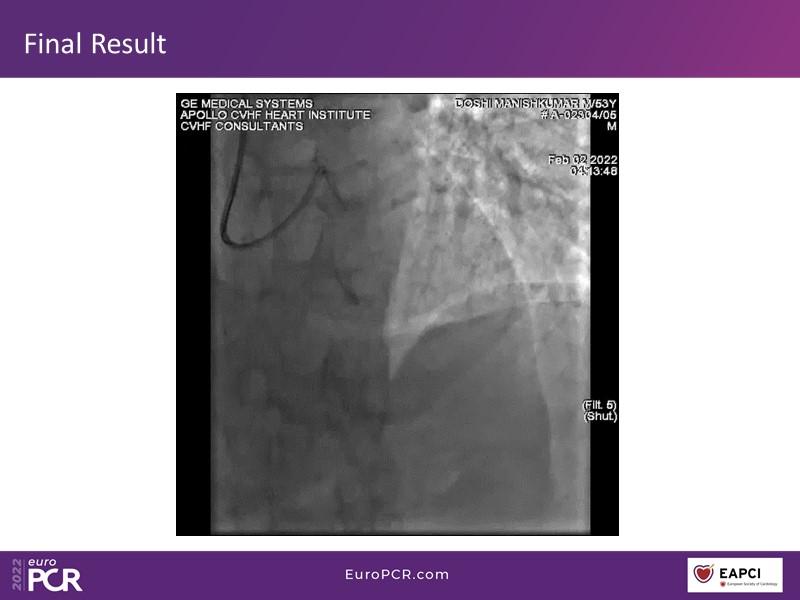

- To know why sirolimus coated balloon is the ideal choice in native vessel disease treatment through a case presentation